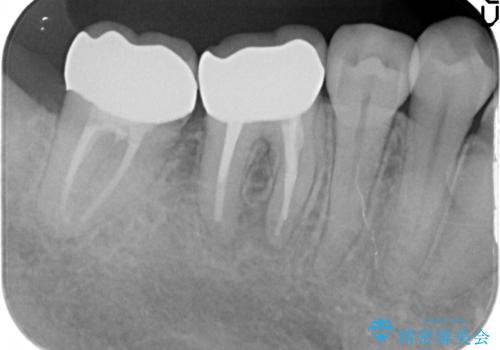

- 奥歯が欠けてしまったので診て欲しいといらっしゃった方の症例です。

再根管治療終了後、オールセラミッククラウンによる補綴を行いました。

- オールセラミッククラウン…¥100,000×2、仮歯…¥10,000×2、ファイバーコア…¥20,000×2費用は治療当時の料金となります

今回用いたオールセラミッククラウンはジルコニアフレームという白い素材の上にセラミックを盛っているため、審美性が非常に高いのが特徴です。

また、ジルコニアは人工ダイヤモンドの材料にも使われているほど高い強度を持っており、そのためオールセラミッククラウンは審美性だけでなく、奥歯やブリッジの補綴も可能とするクラウンです。